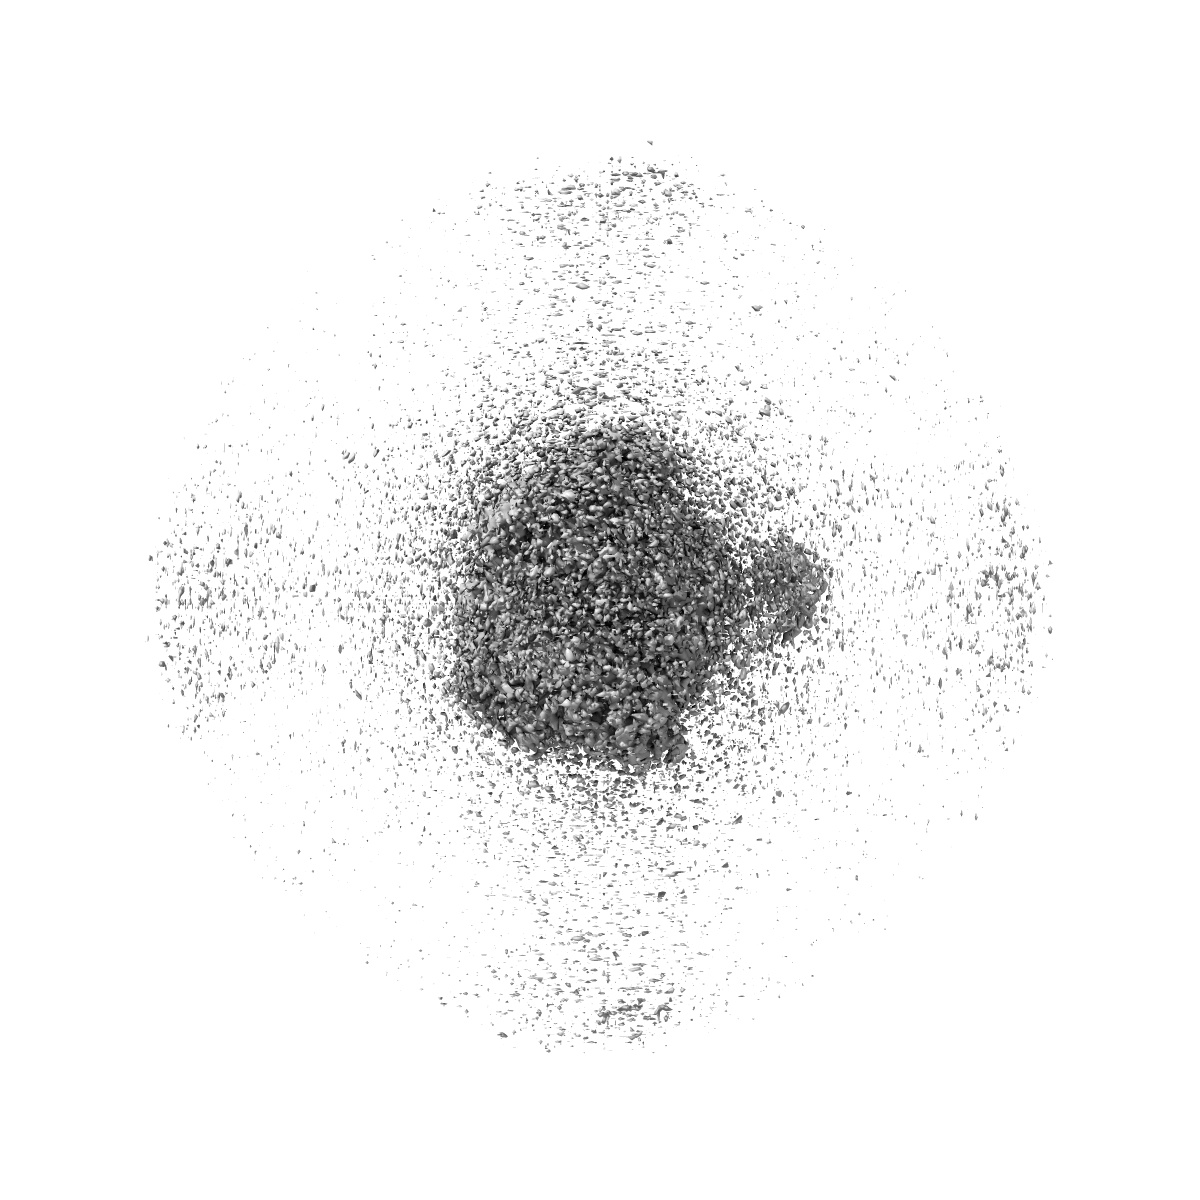

Cryo-EM structure of cancer-specific PI3Kalpha mutant E542K in complex with BYL-719

Single-particle2.77 Å

Sample: Human PI3Kalpha mutant E542K in complex with BYL-719